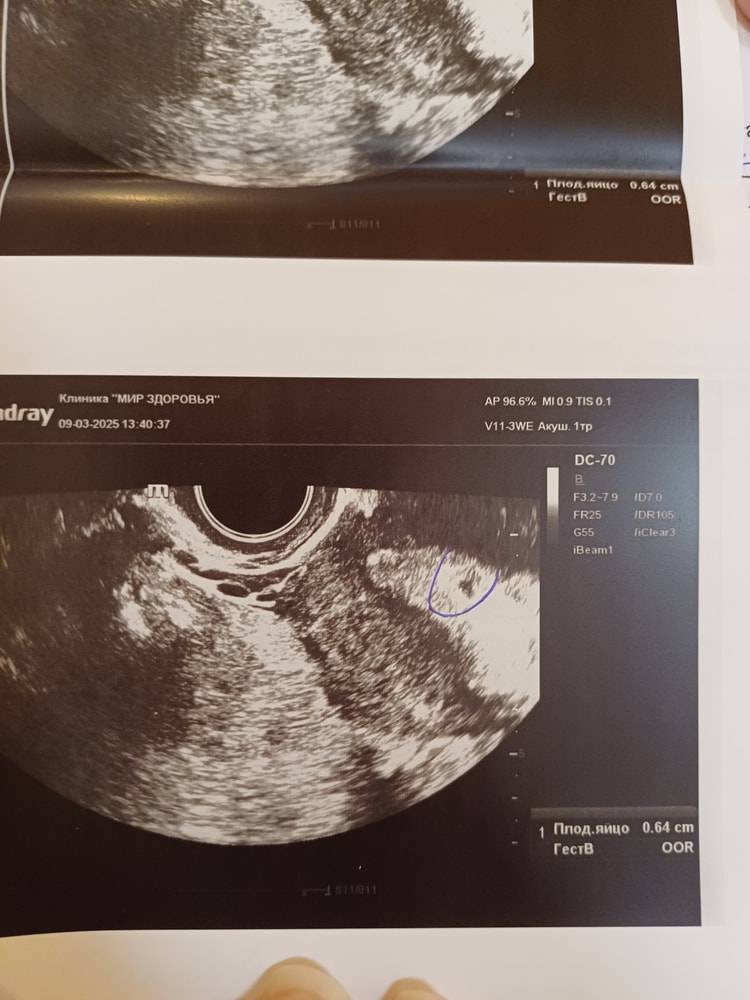

Марина Алташина, и по узи плодное яйцо какой-то страннтй формы ккк мне кажется. Вот выделено ручкой. Не круглое и без ободка. Или

такая форма нормальная?

Galina, оно слишком маленькое для своего срока. Вы все сделали правильно, не надо себя винить.

Марина Алташина, спасибо большое. И само по себе пя не круглое и нет ободка. Другая врач сказала даже для поздней овуляции очень маленькое и маловероятно.что будет развиваться нормально. Ни токсикоза.никаких признаков я тоже не чувствовала как было в прошлые беременности. Врач сказала лучше сразу таблетки.чем потом чистка/вакуум. А можно еще спросить. Мне давали три таблетки мифепркстона (600 мг), я так поняла, т.к. препарат производства Россия, это вреднее для организма, чем если бы был препарат Китай 1 таблетка 200 мг? После Российского препарата же тоже можно спустя 2 цикла планировать?

Марина Алташина, а можно еще спросить, а вот такая форма плодного яйв в 6.1 нед 6.4мм без желточного мешка.такая форма пя тоже плохой признак? Я думаю если бы ждала до 8 нед.может появился бы эмбрион, овуляция поздняя

Galina, если эмбриона нет в 6 недель, то в 8 он не появится. Для 6,1 нед размер плодного яйца 6.4 слишком мало.

Марина Алташина, а форма такая размытая пя тоже указывает на замершую? Пя же круглое с ободком бывает. А тут и желточного мешка тоже нет. А имеет значение.что овуляция на 22 день цикла (цикл 34 дня). Узи делалось на 9й день задержки

Марина Алташина, она указывает на замершую? Не круглая и без ободка. Нет желточного мешочка в пя 6 мм